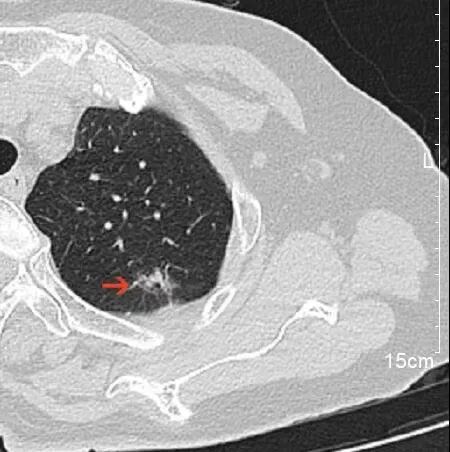

“吴主任,麻烦您给看看,老严是不是和我一样幸运!” 浙大二院解放路院区胸外科吴明主任医师的诊室内今天特别热闹,夏大伯带着他的钓友严大伯前来求医,期望朋友能和自己一样幸运。 事情要回溯到2个月前。年前夏大伯“阳”了一周后,依旧觉得浑身不得劲,来到浙大二院滨江院区做了胸部CT。 不查不知道,一查吓一跳。本来还只是“不得劲”的夏大伯,年三十看到自己的CT报告,当场就感觉四肢无力,呼吸都有些困难了。丰盛的年夜饭,在CT报告“肿瘤不除外”这几个字面前,也变得索然无味。 夏大伯是怎么都在家里待不住了,第二天一大早就再次来到了滨江院区,碰上了过年期间坐诊的胸外科吴明主任医师。 吴明仔细查看了夏大伯的CT,认为这个肺结节看着虽不能完全排除肿瘤,但炎症所致的概率更大。便劝夏大伯放宽心,回去口服抗生素治疗半个月,1个月后再复查胸部CT。 夏大伯“百度”了吴明医生的专家资料后,又听他这么说,悬着的心放下了一半。 待1个月后复查 悬着的另一半心更是彻底放下了 他的肺结节基本消失了 当得知自己的钓友也查出了肺结节,夏大伯二话不说就带着他来到了吴明医生的门诊。 吴明看了严大伯的CT片子,认为虽然他的肺结节中也有炎症成分,但是恶性的可能性也不低。果不其然,经过半个月的抗炎治疗,1个月后严大伯复查了胸部CT,肺结节虽然缩小了,但并未完全消失。 “是不是消炎药不够好?要不要再吃半个月?” “要不要挂盐水?” 严大伯和夏大伯明显还希望通过抗感染治疗,把肺结节治好。 吴明医生告诉他们说,肺结节之间是不同的,需要结合多方面的因素去综合判断。严大伯的这个肺结节恶性的几率还是很高的。 术后,病理果然提示: